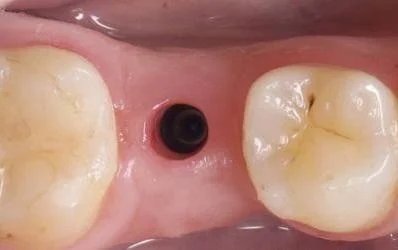

Stock healing abutment in the mouth

Image of a stock healing abutment and the gingival emergence profile created by it.